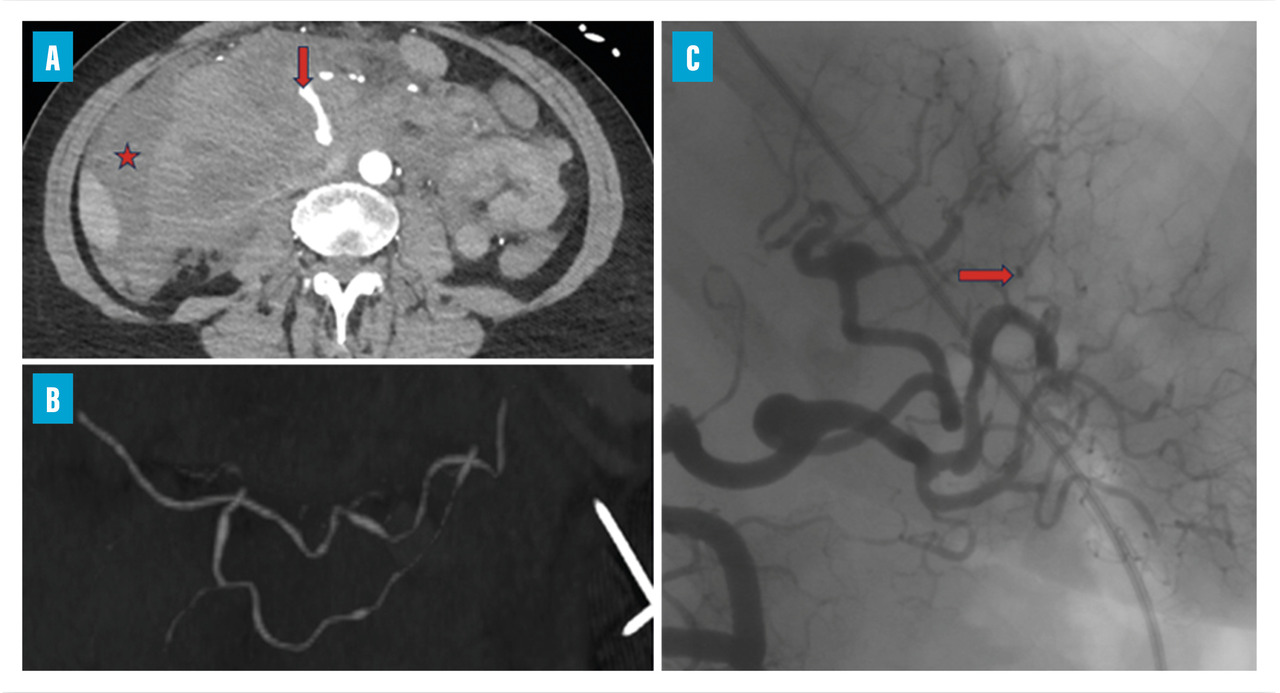

Les atteintes digestives et rénales sont vasculaires, en lien avec des sténoses des moyens vaisseaux, responsables de phénomènes ischémiques et/ou de microanévrismes (fig. 4).6 Leur diagnostic se confirme à l’imagerie, notamment par une angiotomodensitométrie (TDM). L’artériographie, examen de référence, peut s’avérer nécessaire, à visée diagnostique en cas de négativité de la TDM,2 mais surtout à visée thérapeutique, permettant une artério-embolisation en cas d’hémorragie grave.

Les douleurs abdominales, volontiers post-prandiales, sont fréquentes. Elles peuvent être révélatrices de complications sévères telles que les perforations digestives ou les hémorragies intrapéritonéales (fig. 5), gastro-intestinales ou sous-capsulaires. Ces complications s’observent chez 4 % des patients, de même que les cholécystites et pancréatites alithiasiques. Au total, jusqu’à 14 % des patients atteints de PAN peuvent subir un geste chirurgical pour une complication digestive.5,15

L’imagerie artérielle peut suffire à poser le diagnostic, en cas de suspicion clinique et de présence d’anévrismes sacciformes ou fusiformes, de sténoses des artères de moyen calibre, notamment rénales, hépatiques ou digestives.2,4 En première intention, une imagerie non invasive telle que l’angio-TDM ou l’angio-­IRM (en cas de contre-indication aux produits de contraste iodés) est recommandée mais nécessite un regard exercé de la part du radiologue. L’artériographie reste l’examen de référence en cas de doute diagnostique, mais n’est réalisée qu’en deuxième intention, compte tenu d’éventuelles complications, à type d’hématome, de faux anévrismes au point de ponction ou de néphropathie aux produits de contraste.2 Elle peut aussi jouer un rôle thérapeutique, en cas de saignement sévère, permettant de réaliser une embolisation.